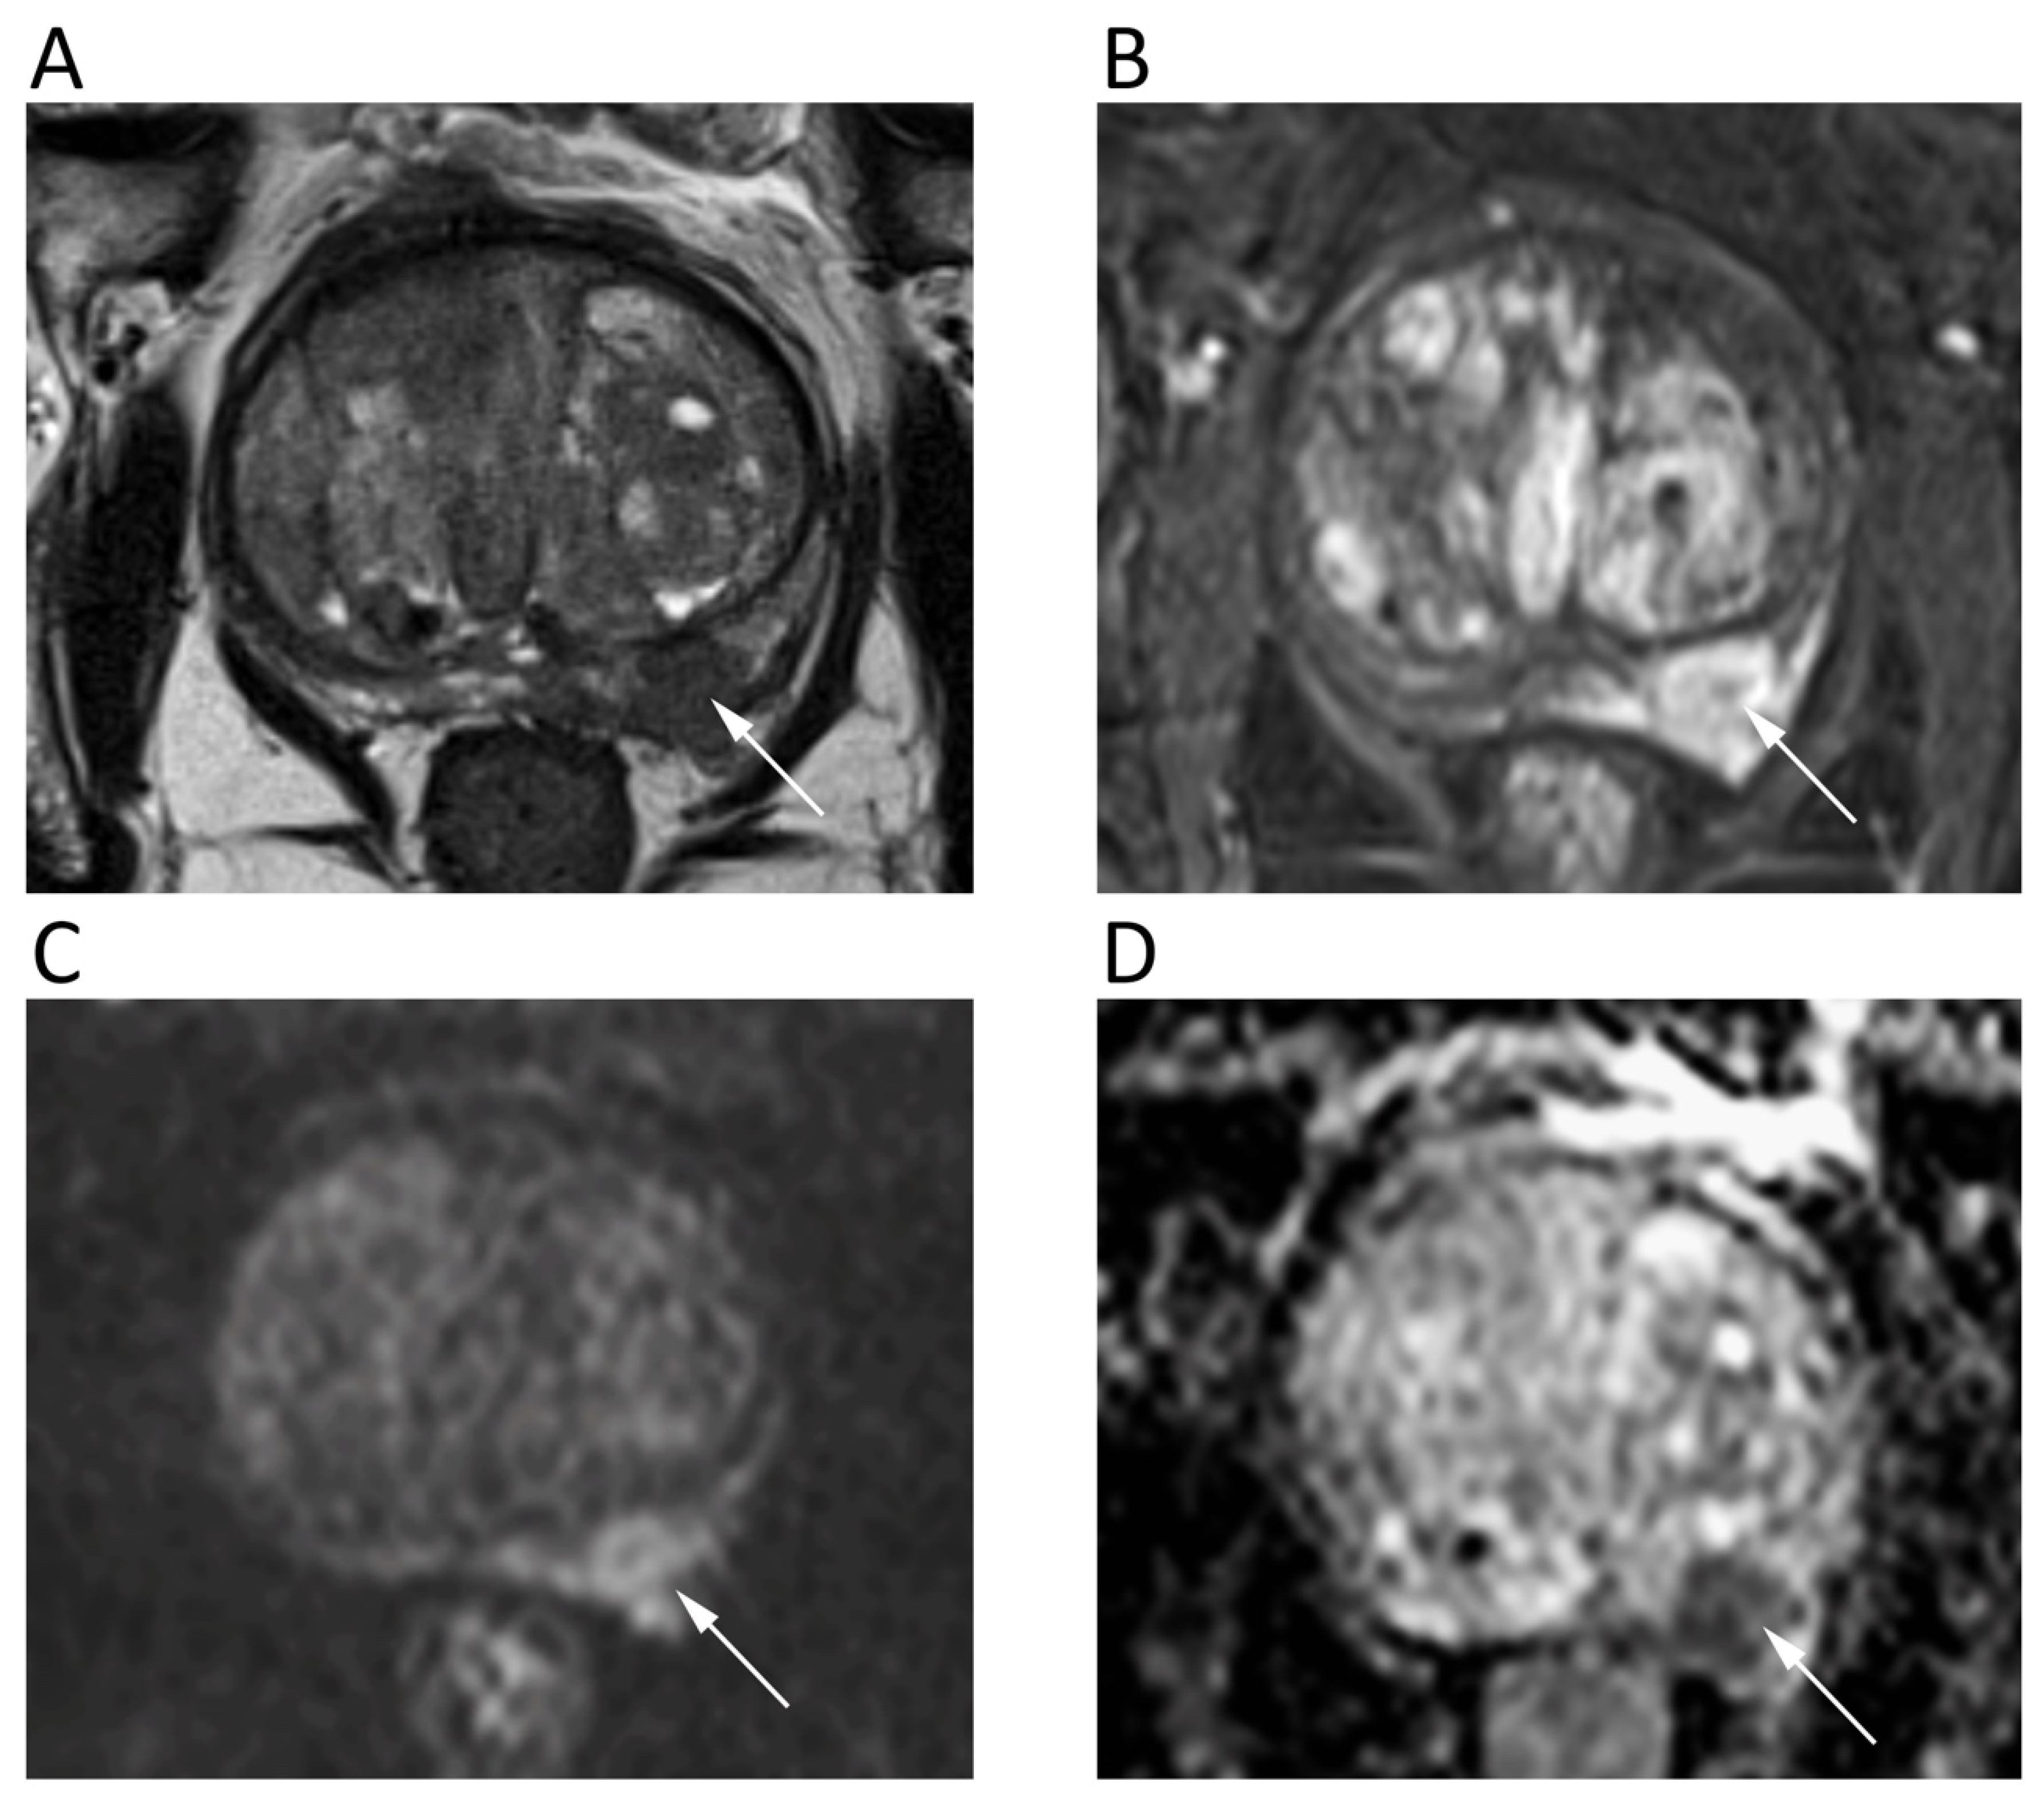

The mpMRI is widely used to detect, localize, and stage prostate cancer (PCa). The prostate imaging reporting and data system (PI-RADS v2.1) for mpMRI is the most common method for standard reporting. It consists of a 5-point scale based on the likelihood that a combination of mpMRI findings on T2-weighted, DWI, and DCE correlates with the presence of a clinically significant PCa [80]. To increase the accuracy of DWI, both ADC map and high-b-value DWI images should be evaluated, generally applying three b values, with the lowest b = 0 and the highest b = 1400/1500, although some authors suggest using b = 2000. Nevertheless, there is no widely accepted optimal high-b-value in the literature. Imaging with higher b-values suppresses healthy background tissue, highlighting PCa tissues with restricted diffusion and lower ADC (Figure 10). Further, it should be considered that transitional zone and peripheral zone tumors may present different perfusion and diffusion parameters [81].

Figure 10.

A 68-year-old male patient with prostate cancer. Axial T2w (A) and post-contrast fat-suppressed T1w (B) images show a hypointense nodule in the left peripheral zone (arrows) with high signal intensity on b = 1000 DWI image (C) and restricted pattern of diffusion on the corresponding ADC map (D).

Although ADC has shown to inversely correlate with histologic grades, there is considerable overlap between benign prostatic hyperplasia, low-grade PCa, and high-grade PCa. Qualitative visual assessment of DWI is often used as the primary method. An ADC threshold of 750–900 mm2/s has been proposed to ease the differentiation between benign and malignant prostate tissues, with ADC below it having been correlated with clinically significant PCa [80]. Authors have identified a moderate correlation between ADC and Gleason score of PCa in the peripheral zone and weak correlation in the transitional zone (pooled correlation coefficient of 0.48 and 0.22, respectively) [82], although better results have been reached using the ADC ratio as a more accurate and reproducible method [83]. Previous studies reported similar (p = 0.83) diagnostic performance of biparametric MRI without DCE (pooled sensitivity and specificity of 0.74 and 0.90, respectively) and mpMRI (pooled sensitivity and specificity of 0.76 and 0.89, respectively) for the diagnosis of PCa, suggesting the former as a valuable first-line imaging test due to its robust sensitivity [84]. Notably, Gong et al. have recently reported the high diagnostic performance of radiomic models based on biparametric MRI to non-invasively identify high-grade PCa, with accuracy ranging from 0.787 and 0.801 [85]. However, despite the limited role of DCE in determining the overall PI-RADS category, in some instances DCE may assist in the detection of PCa and the PI-RADS Committee suggests to reserve biparametric MRI only for selected clinical scenarios.